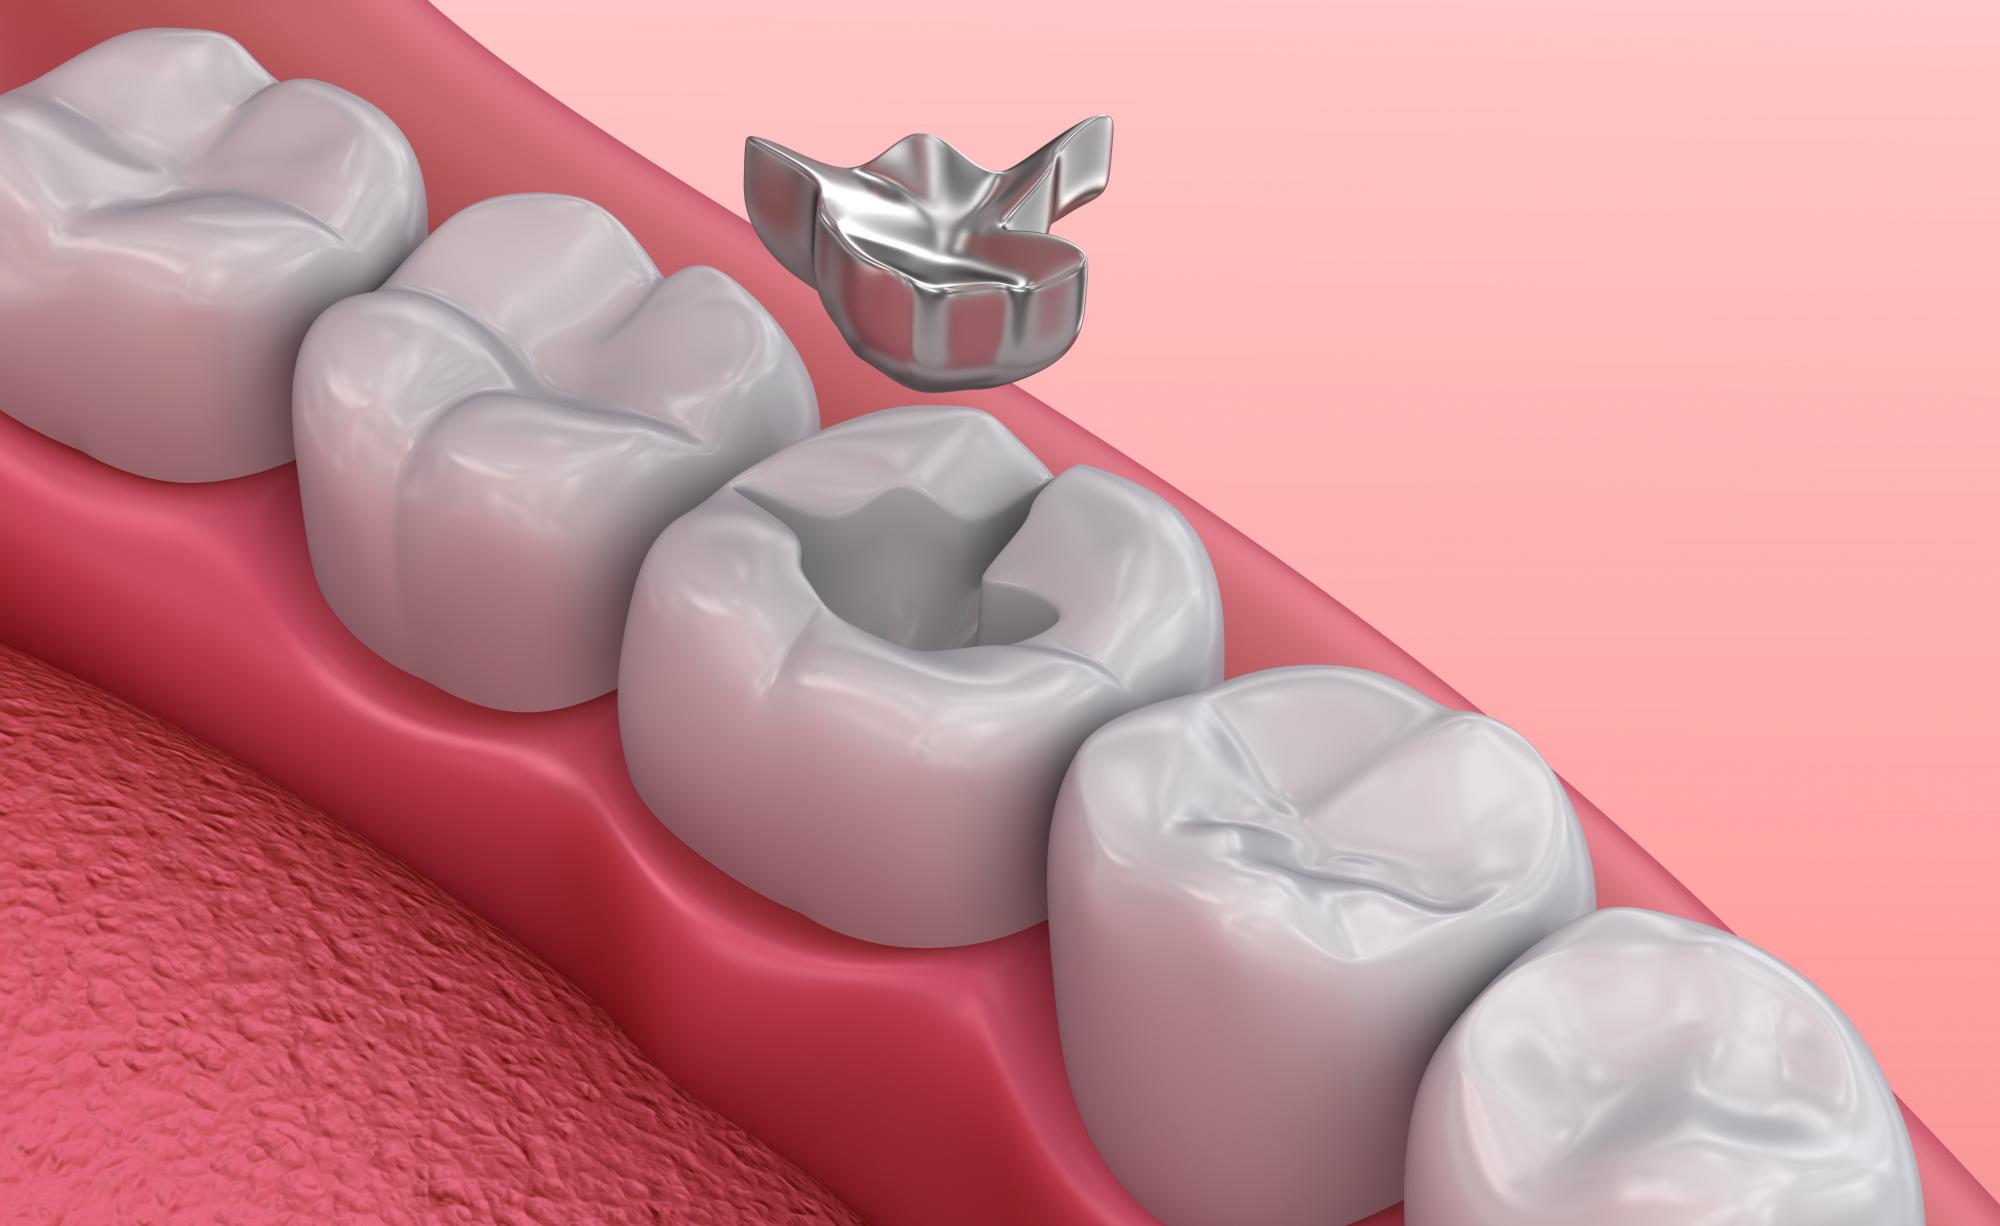

Циркониевые коронки и штифты: современные решения в стоматологии

Раздел: Необычные решения